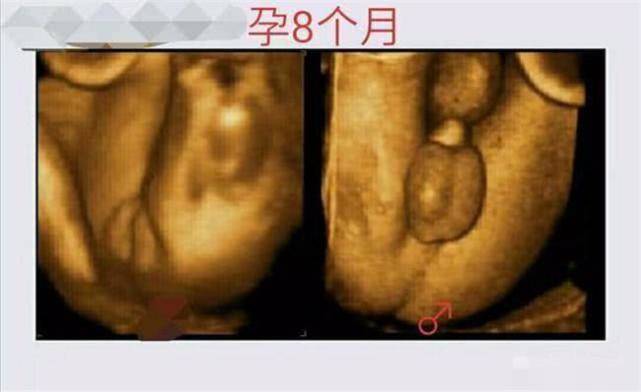

当携带X染色体的精子与卵子结合,则宝宝是女孩;当携带Y染色体的精子与卵子结合,则宝宝是男孩。胎儿发育到孕5-6周时,会逐渐形成生殖腺,到孕8周时,如果受精时是Y染色体,则生殖腺会往睾丸方向发育;如果受精时是X染色体,则生殖腺往卵巢方向发育。